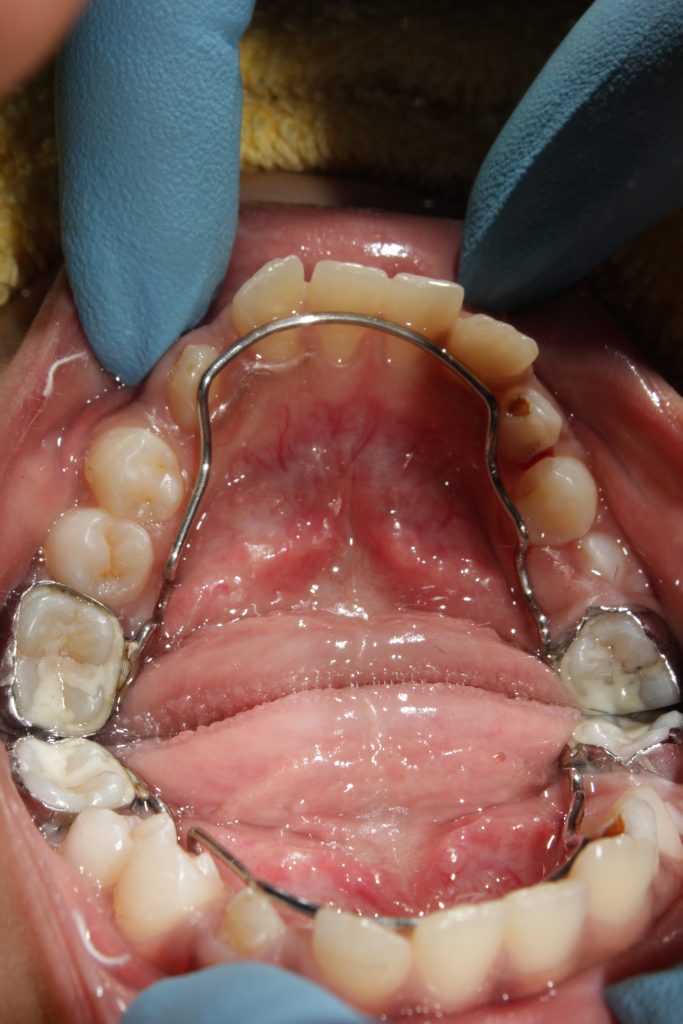

Space Maintainers Barbara J. Utermark, D.M.D. Martinez

The effectiveness of thermoplastic retainers as a space maintainer Ada Code Removal Of Space Maintainer Replacing current code d1550—recement or rebond space maintainer. Removal of plaque, calculus and stains from the tooth structures and implants in the primary and transitional dentition. Cdt codes for dental space maintainers. The american dental association’s cdt procedure codes and nomenclature have been updated for 2024. This update includes 14 new codes, one new category. A passive appliance, usually cemented. Ada Code Removal Of Space Maintainer.